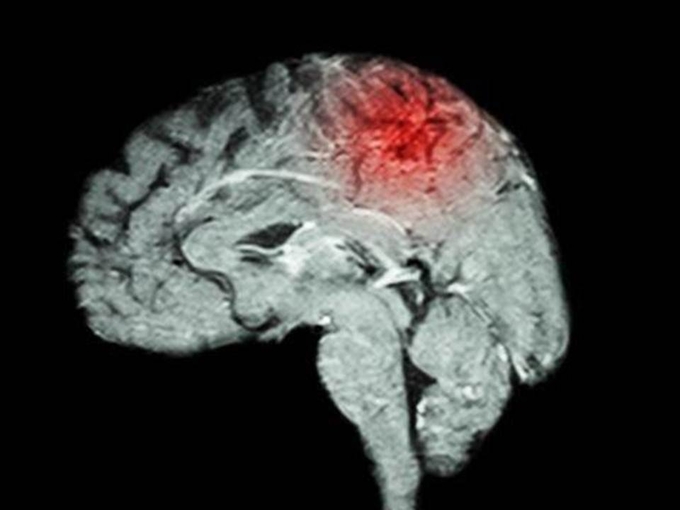

오늘은 생명과도 연결되는 뇌졸중 전조증상에 대해 알려드리겠습니다. 뇌 손상을 유발하는 대표적인 질환이 뇌졸중입니다. 뇌졸중은 뇌혈관이 막히거나 터져서 나타나는 문제입니다. 뇌혈관이 막히면 뇌경색, 뇌혈관이 터지면 뇌출혈이라고 불립니다. 산소 공급이 원활하지 않기 때문에 뇌세포가 손상될 가능성이 매우 높습니다. 뇌세포 손상 정도에 따라 다양한 합병증이 나타납니다.

뇌졸중은 뇌에 피가 통하지 않거나 뇌에 연결된 혈관이 파열되어 발생하는 증상을 말하는데, 이로 인해 뇌의 기능에 장애가 생기고 몸에 장애가 생기거나 심하면 사망에 이르는 질환입니다. 뇌졸중이 발생하면 뇌신경에 이상이 생기기 때문에 손상된 뇌 부위에 연결된 신체 부위도 움직이기 어려워집니다.

뇌졸중의 원인인 대표적인 질환은 고혈압입니다. 뇌경색 환자의 60% 이상, 뇌출혈 환자의 70~80%가 고혈압을 동반하고 다음으로 흔한 원인은 당뇨병으로 뇌졸중 환자의 약 30%에서 나타납니다. 후천적 요인이 뇌졸중 원인의 90%를 차지하며 뇌 어느 부위에 이상이 생겼느냐에 따라 초기 증상이 다양한 양상으로 나타납니다.